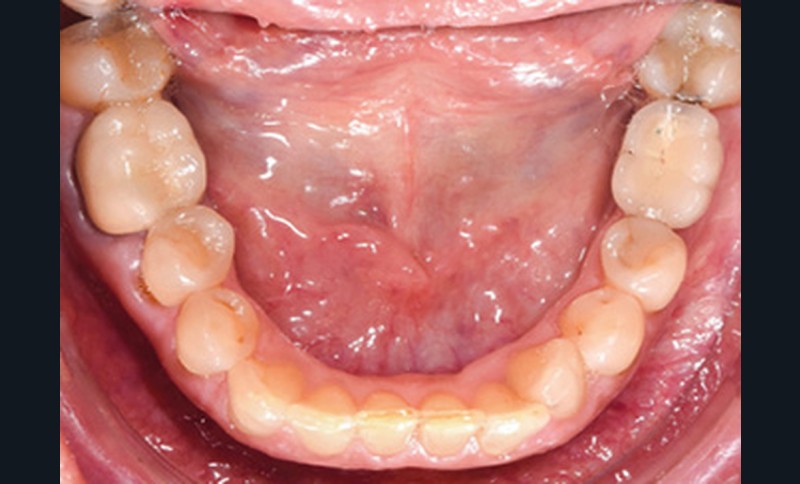

Examen endobuccal (fig. 2a-e)

L’arcade maxillaire est asymétrique et parabolique. Elle présente une mésio-position du secteur 1. On note des rotations mésio-vestibulaire de 13 et disto-vestibulaire de 23 et une palato-version incisive. Les restaurations prothétiques sur 11, 16 et 24 semblent à refaire. L’arcade mandibulaire est asymétrique et parabolique avec une couronne sur implant en 36.

Dans la dimension transversale, on constate une endoalvéolie maxillaire. Dans la dimension sagittale, on observe une classe II plus importante à droite où elle est complète de 5 mm. Le surplomb est absent et la supraclusion totale (6 mm) par supra-alvéolie mandibulaire.